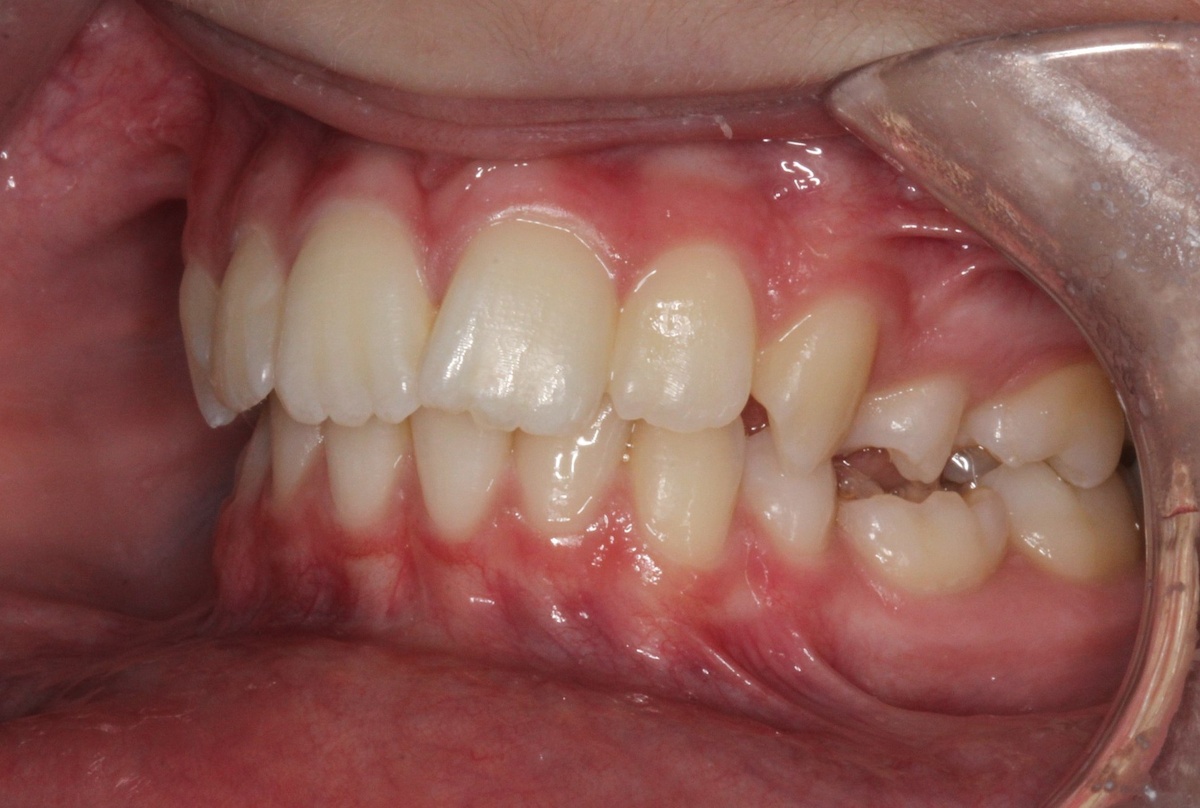

Пациент с дистальной окклюзией, глубоким прикусом, отсутствием части постоянных зубов (первичная адентия), наличием молочных зубов на их месте — сложная окклюзионная схема.

Лечение заняло 3,5–4 года.

Удалось добиться красивой улыбки, правильного резцового перекрытия и хороших окклюзионных контактов.